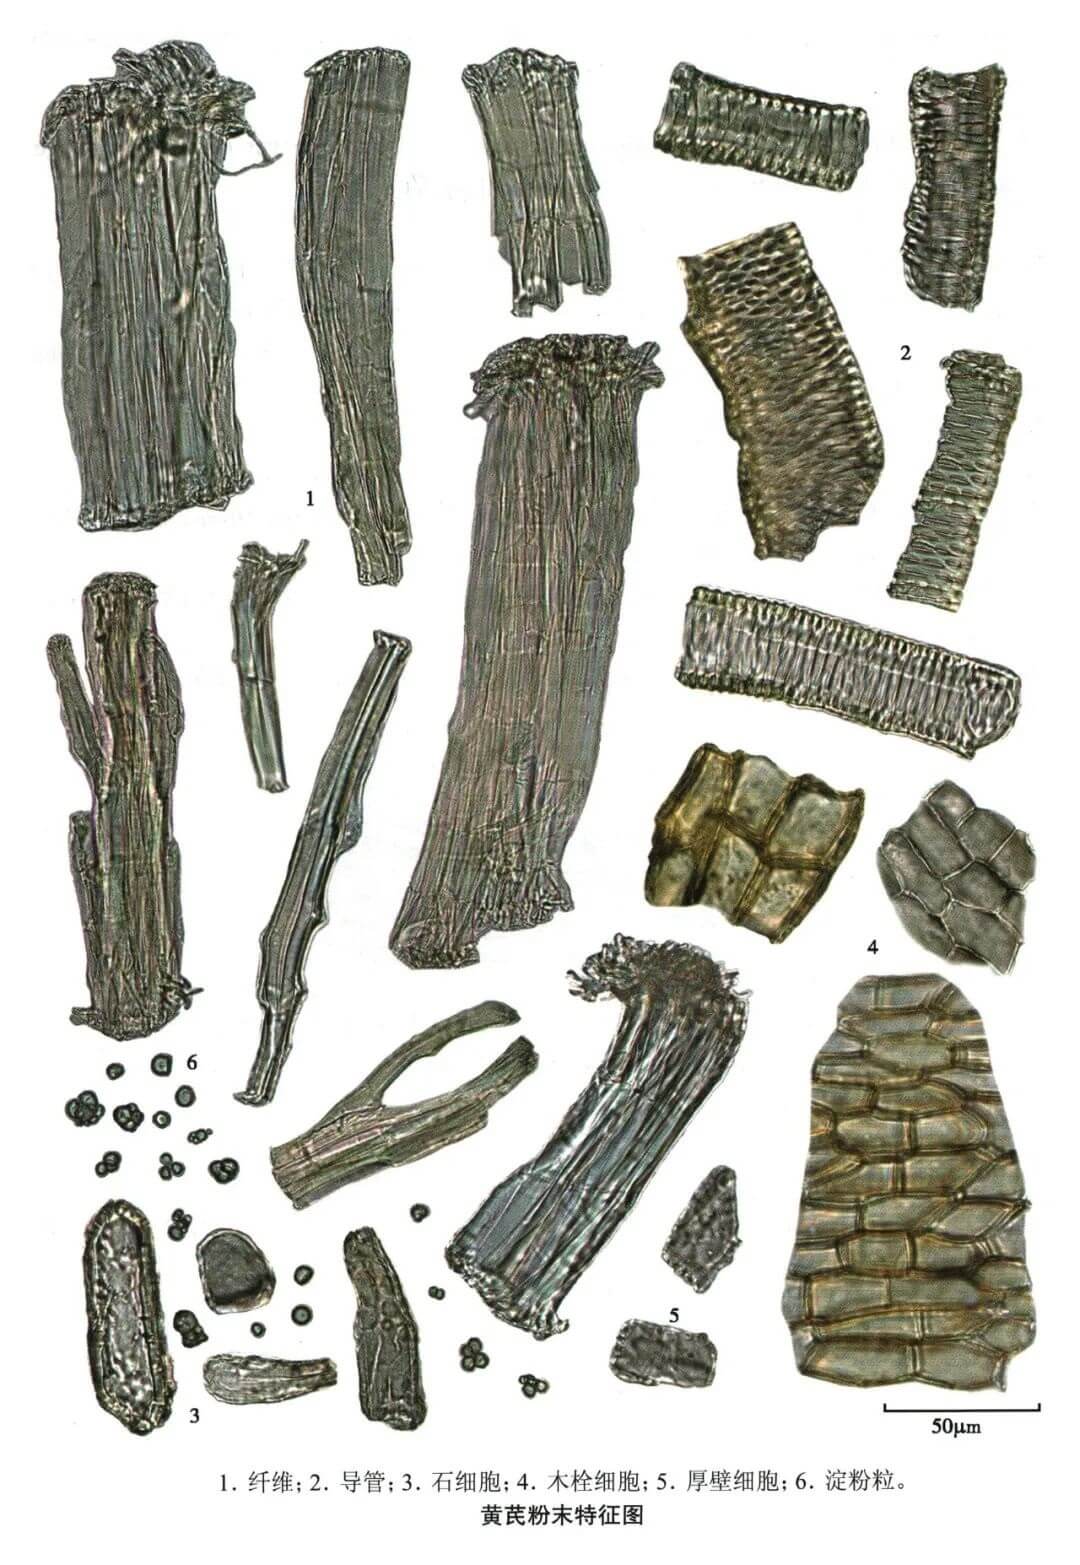

黄芪

| 黄芪 |

|---|

| 【参考标准】 《中国药典》2020年版一部 |

| 【显微鉴别】 粉末黄白色。纤维成束或散离,直径8~30μm,壁厚,表面有纵裂纹,初生壁常与次生壁分离,两端常断裂成须状,或较平截。具缘纹孔导管无色或橙黄色,具缘纹孔排列紧密。石细胞少见,圆形、长圆形或形状不规则,壁较厚。 |

| 【显微重点】 扫帚状的纤维;石细胞较难找到。 |

| 【图谱来源】 《中药成方制剂显微图典》 |